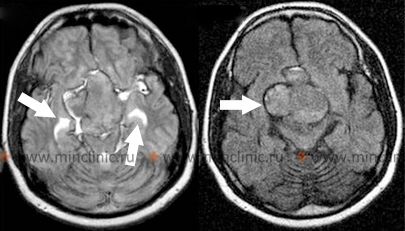

სისხლჩაქცევა თავის ტვინის სიმსივნეში

პირველად ან მეტასტაზურ თავის ტვინის სიმსივნეში უშუალოდ სისხლდენა (ინტრატუმორული სისხლჩაქცევა) ზოგჯერ შეიძლება იყოს საწყისი კლინიკური გამოვლინება, რომელიც იწვევს ინტრაცერებრული ნეოპლაზმის დიაგნოზს [1, 6]. თავის ტვინის სიმსივნეების გარკვეული ტიპები უფრო მეტად არიან მიდრეკილნი სისხლჩაქცევებისკენ, ვიდრე სხვები [6]. სისხლდენის შედარებით მაღალ რისკთან ასოცირებული ხშირი მეტასტაზური თავის ტვინის სიმსივნეები მოიცავს ქორიოკარცინომას, ავთვისებიან მელანომას, თირკმელუჯრედოვან კარცინომას და ფილტვის კიბოს გარკვეულ ტიპებს (ბრონქოგენური კარცინომა)[1, 6]. პირველად თავის ტვინის სიმსივნეებს შორის, გლიობლასტომა მულტიფორმე (ყველაზე გავრცელებული ავთვისებიანი პირველადი თავის ტვინის სიმსივნე მოზრდილებში) და, უფრო იშვიათად, მედულობლასტომა (ხშირი ავთვისებიანი თავის ტვინის სიმსივნე ბავშვებში, ტიპურად განლაგებული ნათხემში) ცნობილია, რომ ზოგჯერ ვლინდება ან უვითარდება ინტრატუმორული სისხლჩაქცევა[1, 6].